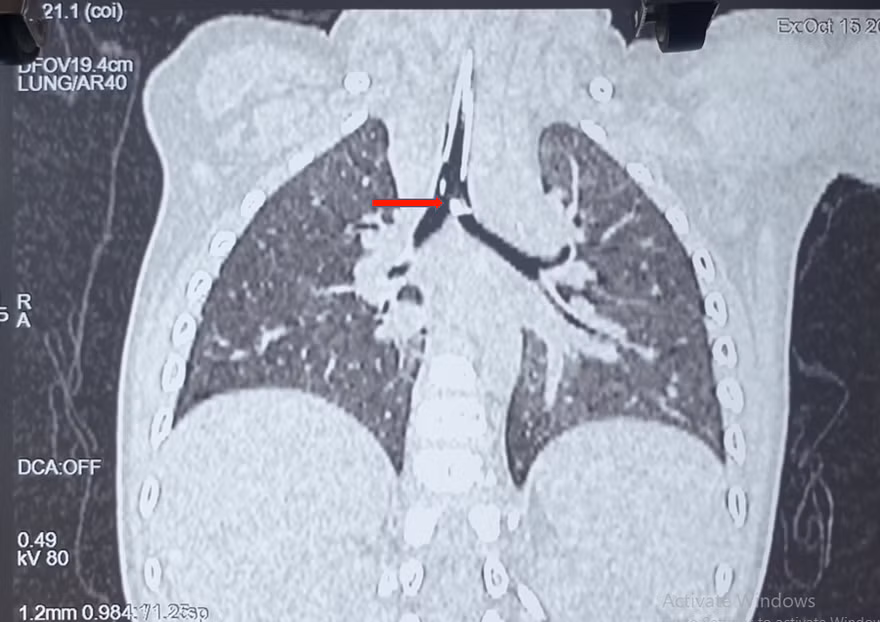

| Mảnh xương lớn ghim vào thành phế quản của bệnh nhi được phát hiện trên hình ảnh CT-Scan |

Các bác sĩ đã tiến hành chụp CT-Scan phổi kiểm tra thì phát hiện dị vật có kích thước lớn (0,5x1cm) nằm ở ngay vị trí chia đôi khí quản thành phế quản gốc bên phải và trái. Sau khi hội chẩn liên chuyên khoa, các bác sĩ đã quyết định thực hiện nội soi đường thở cấp cứu cho bệnh nhi. Mảnh xương sắc nhọn đang ghim vào thành phế quản đã được ê kíp bác sĩ gắp ra ngoài thành công. Ngày 18/10, bệnh nhi đang tiếp tục được điều trị tại khoa Hồi sức Ngoại, tình trạng sức khỏe dần bình phục.